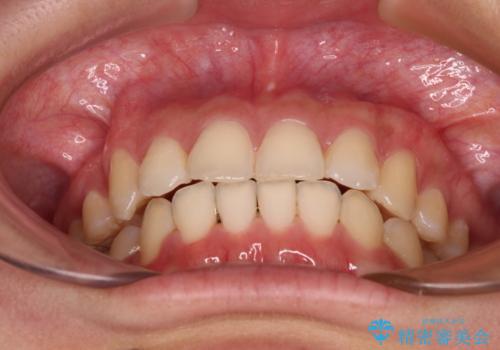

骨格的に下顎が左側に変位していたため、上下正中を合わせることは困難であることは分かっていましたが、可能な限り合わせることができました。

骨格的なズレがあると仕上げの段階で奥歯の咬み合わせが不安定となるため、予定よりやや長期間となりました。